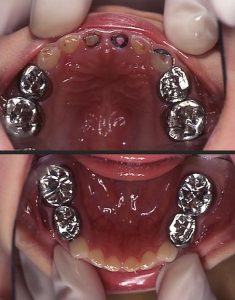

しかし口腔内には、C2・C3が14本も見られる。

(図4 処置終了後の口腔内写真)

処置終了後の口腔内写真